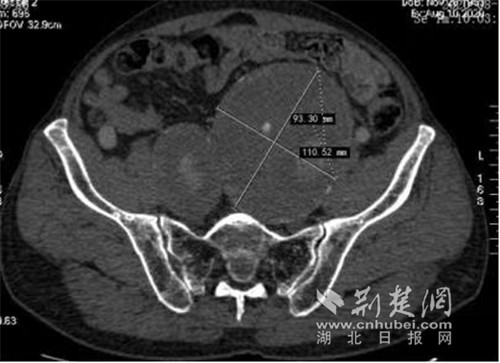

患者双侧巨大髂内动脉瘤、左侧髂动脉瘤体最大直径达110mm。通讯员供图

邓宏平介绍,由于陈先生主动脉瘤瘤颈扭曲严重、合并双侧巨大髂总动脉瘤、双侧巨大髂内动脉瘤,要根治此病,外科开放手术范围广、创伤大。常规微创手术技术复杂存在臀肌、肠道缺血坏死及生殖动脉、下肢动脉缺血风险。而腔内手术既要完全隔绝动脉瘤、又要保留至少一侧髂内动脉,需要周密的手术计划和娴熟的腔内手术技巧。